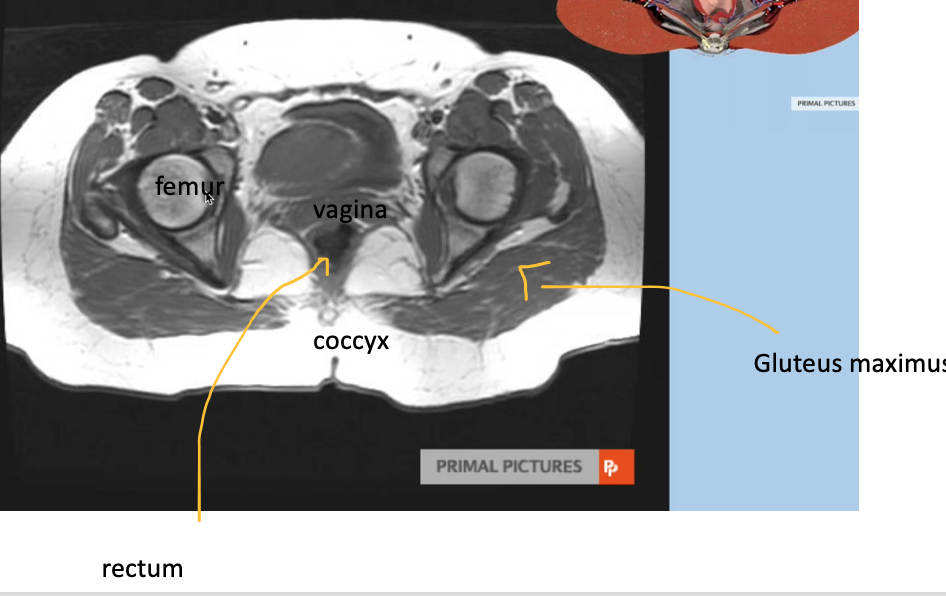

Name the imaging modality & view

Female MRI coronal

34

Name the imaging modality & the plane

Axial female MRI, pelvis